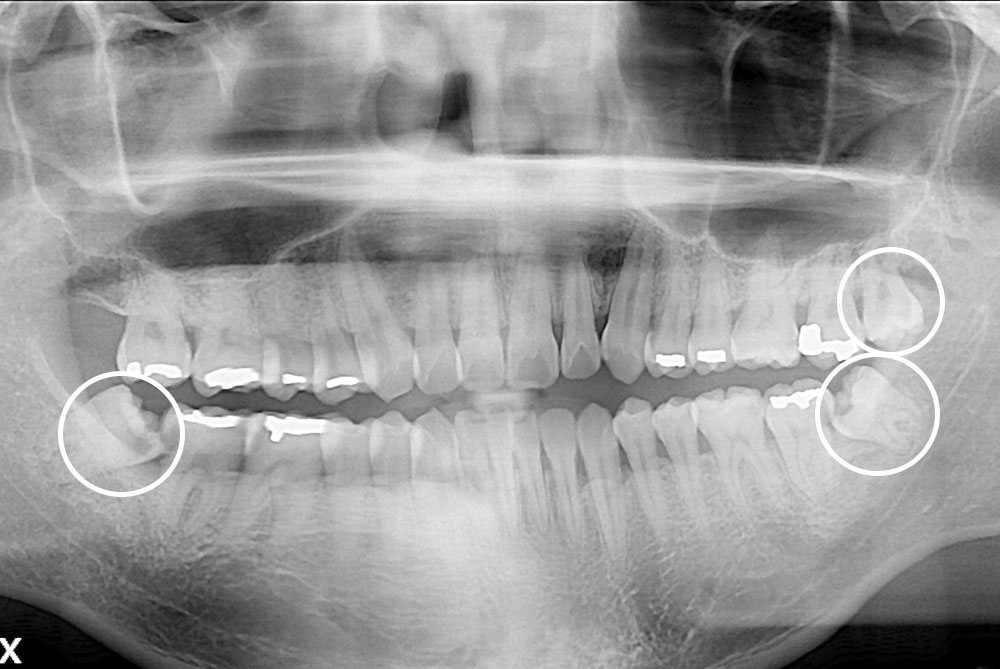

[사랑니] 매복 사랑니 발치

치료전 : 2019-11-05